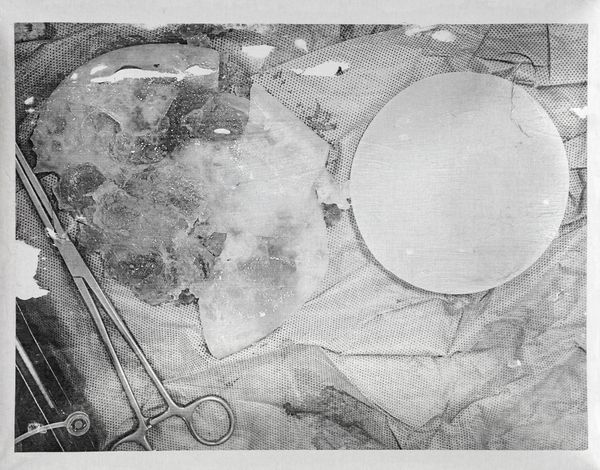

This critical analogy is particularly evident in the widespread use of silicone implants, whose background is not only symbolic but also immunological. ASIA syndrome, described by Shoenfeld in 2011, shows how these adjuvants can trigger systemic reactions: chronic inflammation, autoantibody production, and an increased risk of serious diseases, with explantation being the only possible remedy. What is offered as a promise of beauty ends up, in many cases, becoming a “wound.”

According to the FDA (Food and Drug Administration), one in five patients who receive breast implants have them removed after 10 years due to complications such as ruptures, deflation, or leakage, and painful contraction of the scar tissue around the implant, known as capsular contracture. And this number of injuries has been increasing: from 4,567 in 2017 to 8,242 during the first half of 2018 (Infobae, 2018).

The project is configured as a form of denunciation, a space where the work establishes a dialogue with the testimonies of those who have experienced these bodily transformations. Their stories allow us to perceive in a tangible way how these interventions affect not only the surface of the body, but also its biology and subjective experience: the feeling of vulnerability, the systemic effects, the physical and emotional scars, which are not simple individual accidents, but expressions of a social and aesthetic logic that prioritizes appearance over the integrity of the body.